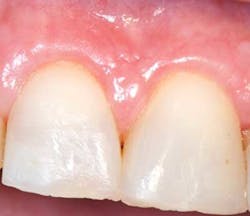

There is certainly no panacea for treatment, but we have found this combination therapy provides our patients with long-term predictable, stable results. Our preferred treatment method for gingival recession defects affecting one to four teeth is to use a tunneling technique in combination with a subepithelial connective tissue graft, enamel matrix derivative, and a coronally advanced flap (figures 4-9). When treating four or more teeth, or if a patient is opposed to harvesting a SCTG, we use a tunneling procedure in conjunction with an acellular dermal matrix graft, enamel matrix derivative, and a coronally advanced flap.